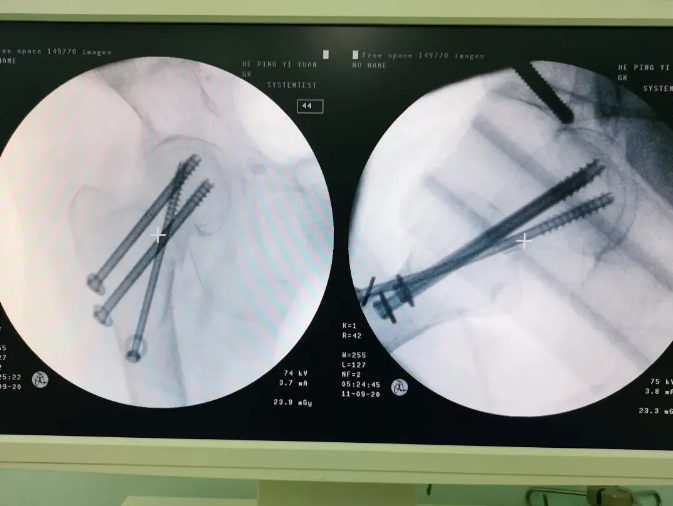

規(guī)劃入路

天璣機器人置入螺釘

螺釘置入后

天璣?骨科手術(shù)機器人的加入,能夠協(xié)助醫(yī)生為需要進行手術(shù)的患者提供更安全、優(yōu)質(zhì)、高效的醫(yī)療服務(wù),幫助患者清除病灶,守護患者健康,提高患者生活質(zhì)量。在天璣?骨科手術(shù)機器人的協(xié)助下,術(shù)中患者切口僅三個小孔,出血量少;術(shù)后陳婆婆經(jīng)一段時間的康復(fù)訓(xùn)練便可下床活動,目前已康復(fù)出院。